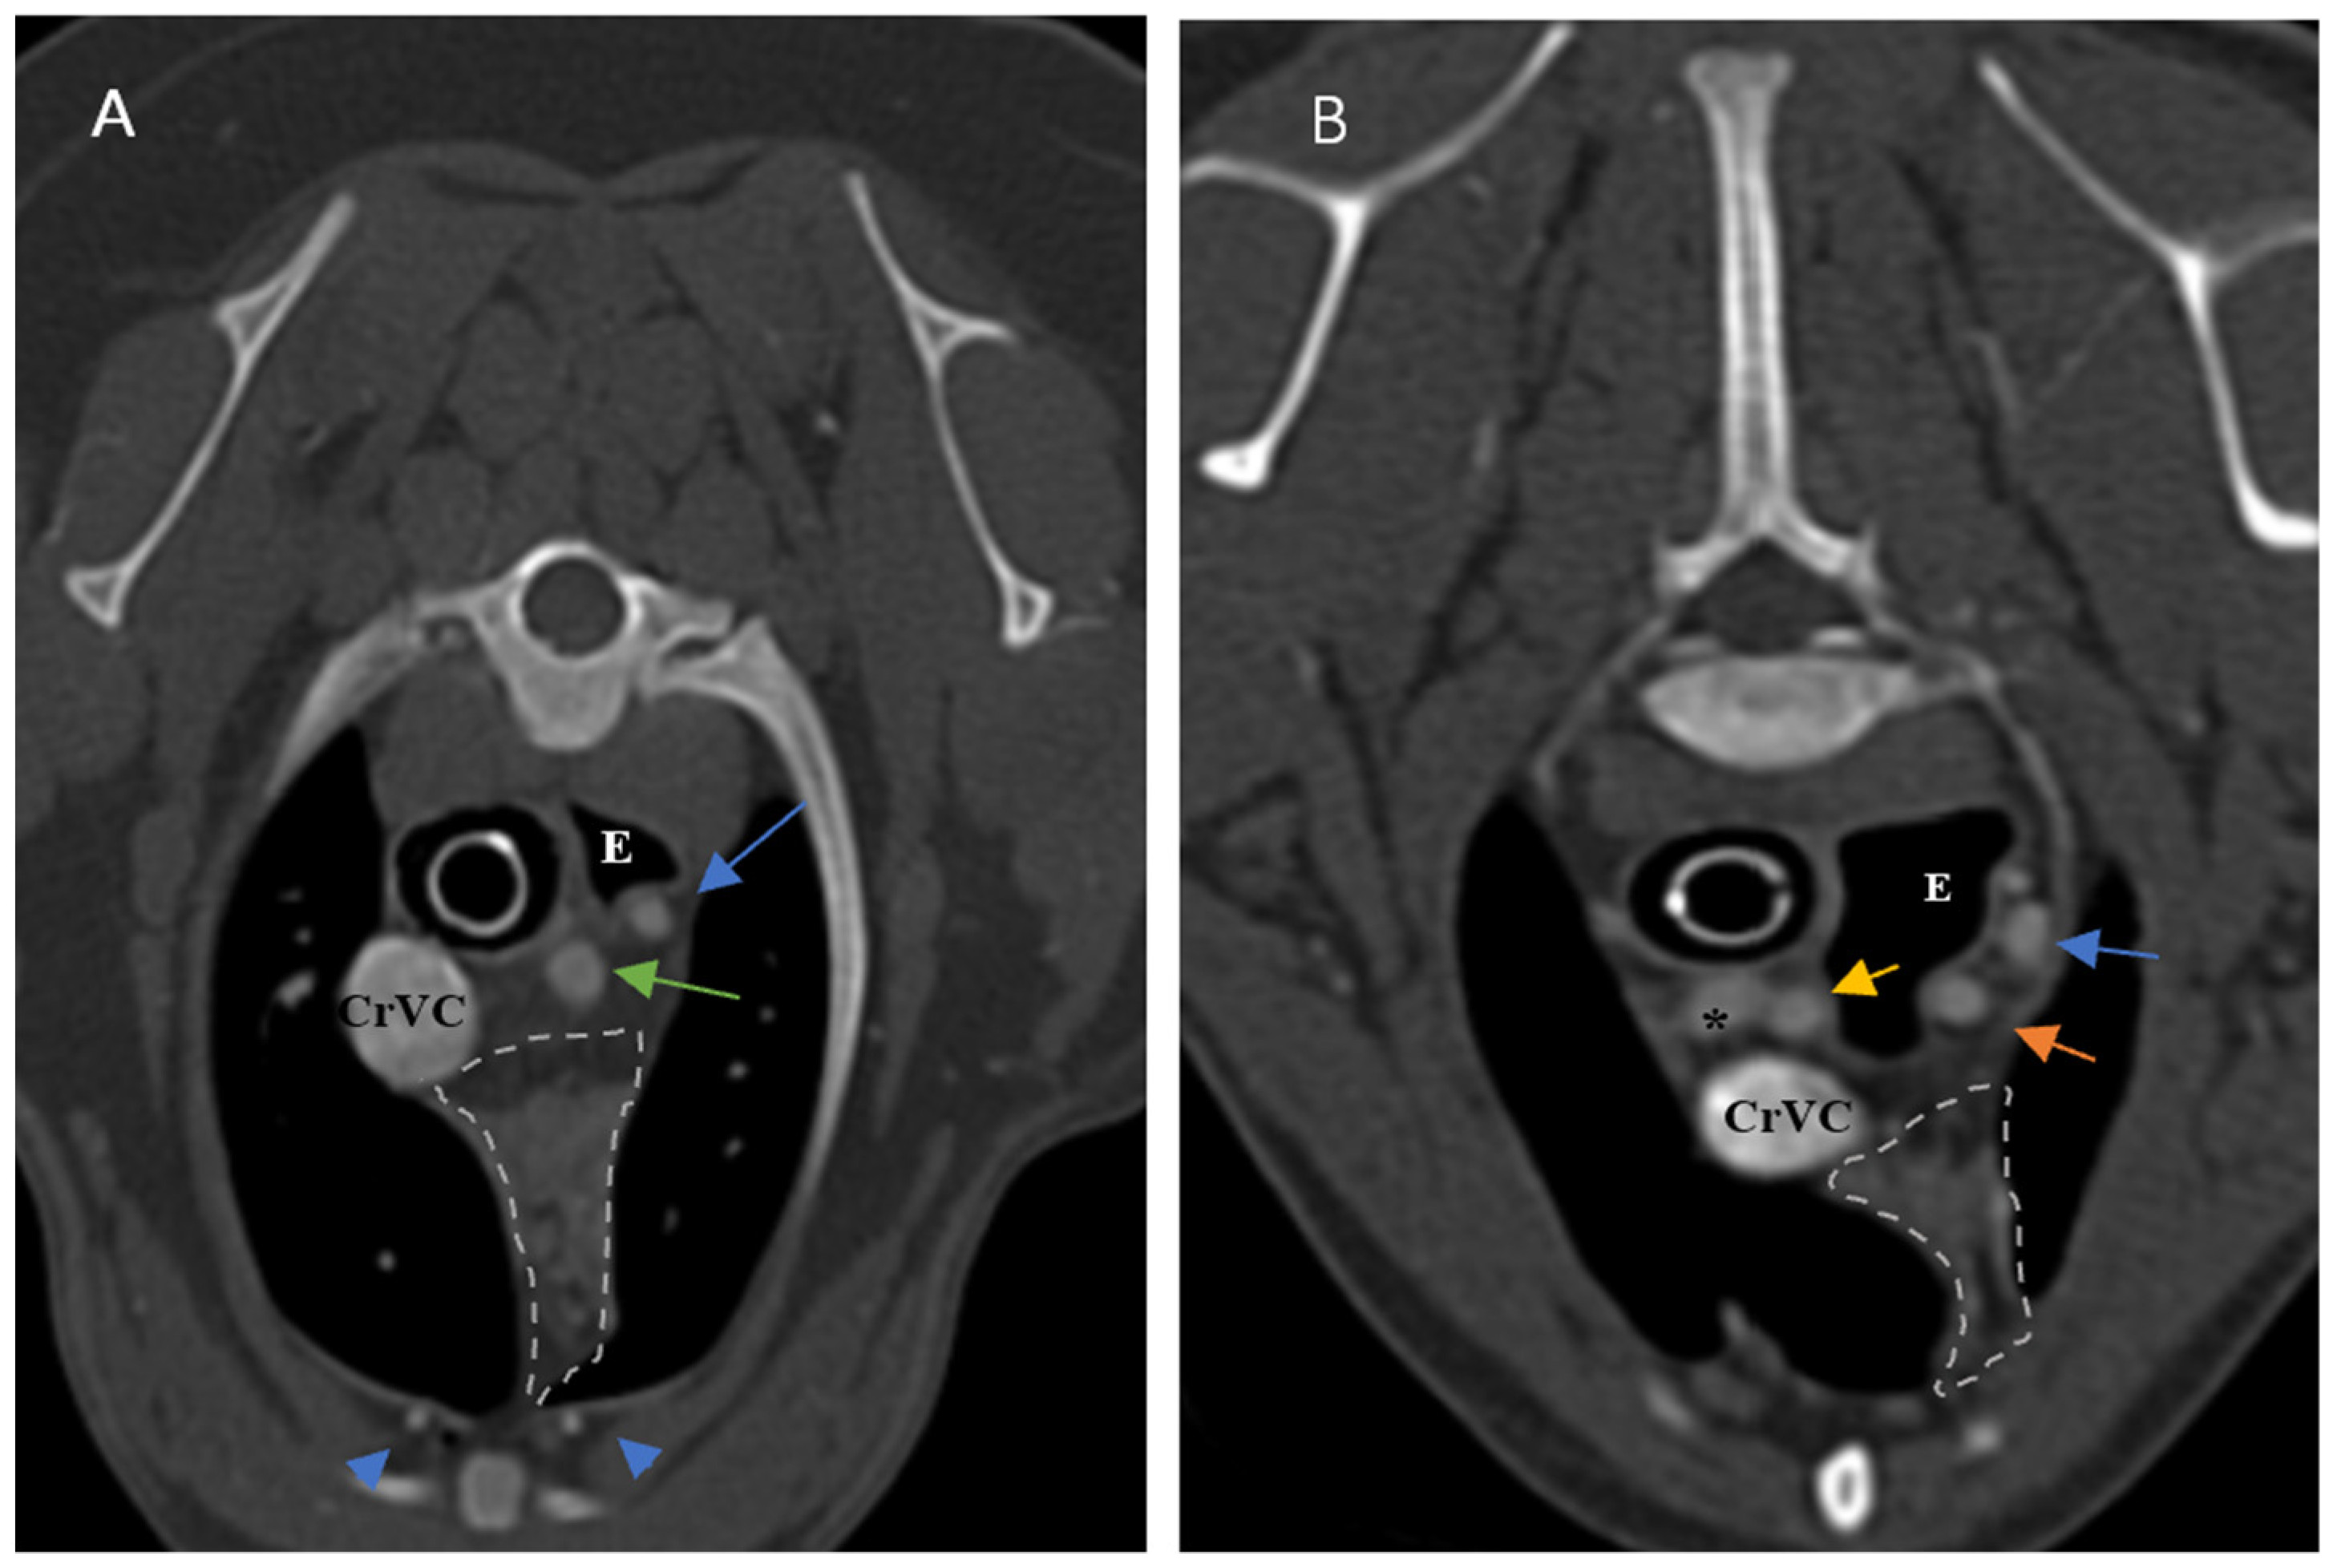

Figure 5. Demonstration of visibility and topographic location of grade 2 thymus in contrast-enhanced transverse sections of the thoracic region at the level of T3 in both patients. (A): One-year-old female mixed-breed dog with a visible, grade 2, wedge-shaped thymus with midline predominancy, mottled appearance and concave border (CT number: 75). (B): Two-year-old female mixed-breed dog with a visible, grade 2, wedge-shaped thymus with left-sided predominancy, mottled appearance and concave border (CT number: 79). Light grey dash lines illustrate thymic borders. CrVC: cranial vena cava, E: esophagus (which is dilated due to general anesthesia), blue arrow: left subclavian artery, green arrow: brachiocephalic trunk, blue arrowheads: internal thoracic arteries, yellow arrow: right common carotid artery, orange arrow: left common carotid artery, and asterisk: right subclavian artery.